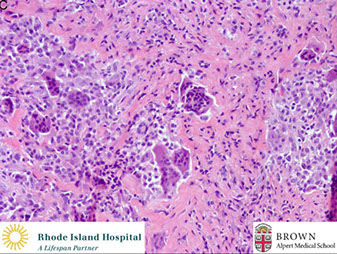

Micro: Spindle-shaped cells c MNGCs with uniform scattering

- mononuclear cells and GC's have similar nuclei and uniformity of cytologic features, can have 50-100 nuclei per cell, lacking atypia

IHC: H3F3B +

DDx: other lesions c MNGCs = brown tumor of hyperparathyroidism (looks identical, need to check parathyroid / renal status), chondroblastoma, solid aneurysmal bone cyst, giant cell reaction, non-ossifying fibroma, giant cell rich osteosarcoma, brown tumor

Giant cell tumor